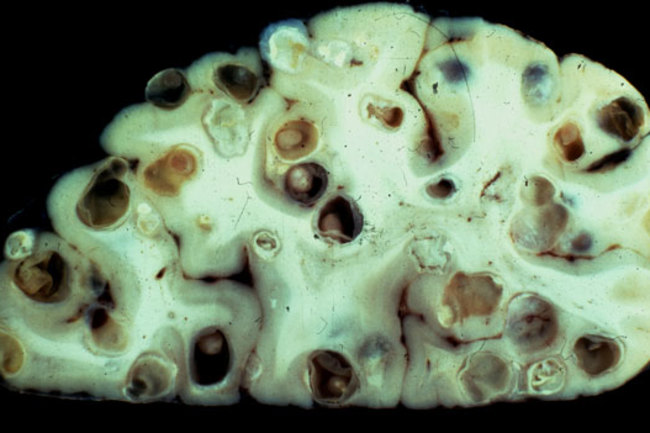

Solium, which develops after ingestion of ova excreted in human feces. It’s convenient and easy to give. However, you may develop symptoms like abdominal pain, nausea, diarrhea, lack of.

Images of tapeworms. Cysticercosis is infection with larvae of T. Experts say that symptoms are usually mild or go unnoticed, so you might not even realize you're infected. Tapeworms have no specialized digestive system but feed on the half- digested food in the intestines by direct absorption through their entire skin surface.

Images (1) Lab Test (0) Tables (0) Videos (0) Taenia solium life cycle Taenia solium infection (taeniasis) is an intestinal infection with adult tapeworms that follows ingestion of contaminated pork. Hookworms and Whipworms thrive in damp soil and the dogs most at risk are those kept on grass runs, especially in warm, humid conditions. Tapeworms are flat, white worms that are made up of tiny segments.